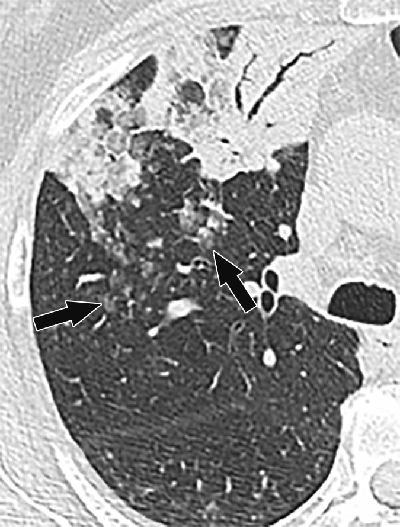

At CT, lesions of such lung metastases spread via the circulatory system are characteristically distributed randomly; round nodules are easily recognizable at CT and pathologic examination. On the other hand, aerogenous metastasis is defined as discontinuous spread of cancer cells from the primary tumor through the airways to adjacent or distant lung parenchyma.

CT features that strongly suggest aerogenous spread include "persistent centrilobular nodules and branching opacities (tree-in-bud nodules), typically with ill-defined margins and ground-glass attenuation," the study team wrote. Well-defined nodules with soft-tissue attenuation are less common in this scenario.

Nodules suggestive of aerogenous spread tend to be clustered, and they always show evidence of growth on serial images, they wrote. In some cases, they progress to confluent air-space disease.

When these metastases are remote from the primary lesion, the nodules tend to have a dependent distribution in the lower lobes. The appearance on CT "reflects cancer cells lining the small airways and alveolar spaces in a lepidic pattern with variable amounts of intra-alveolar material," the authors explained.